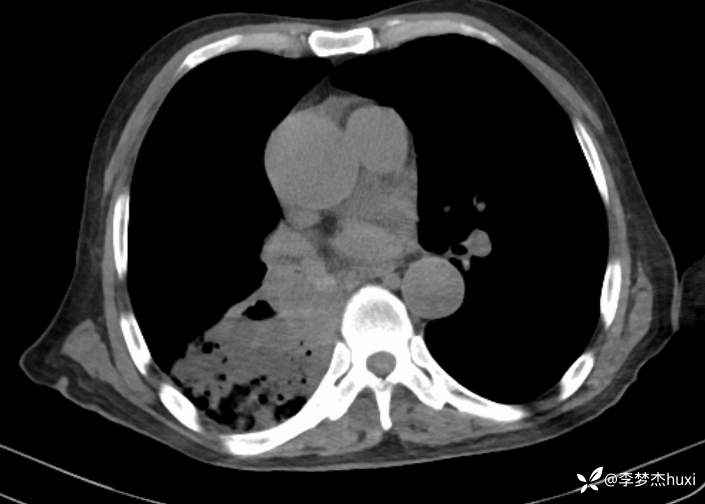

【现病史及既往史】: 1.患者老年 男,患者缘于3小时前无诱因出现意识不清,伴咳嗽、咳痰,痰不易咳出,伴发热,最高体温不详,院外应用“退热药物”(具体不详)治疗,无恶心、呕吐,无大小便失禁,无胸痛,今为求进一步治疗来院就诊,急诊查胸部及头CT:双侧基底节区腔隙性脑梗塞,脑白质稀疏,脑萎缩,脑干密度不均匀,右肺感染首为考虑,占位待除外,建议治疗后复查,右肺中叶局限性炎症,双肺间质性改变,主动脉及冠状动脉钙化,双肺气肿,左肺实性结节,建议复查,纵隔内及右肺门结节,右肺门增大。右肺下叶部分支气管堵塞。右侧胸膜局部增厚并少量积液,甲状腺密度不均匀,胆囊结石,右肾类圆形囊性密度影,建议结合超声。查血常规:白细胞数目 13.91*109/L,BNP前体 1360pg/ml。D-二聚体 0.8pg/ml。以“肺炎”收住院;。

4.辅助检查:急诊查胸部及头CT:双侧基底节区腔隙性脑梗塞,脑白质稀疏,脑萎缩,脑干密度不均匀,右肺感染首为考虑,占位待除外,建议治疗后复查,右肺中叶局限性炎症,双肺间质性改变,主动脉及冠状动脉钙化,双肺气肿,左肺实性结节,建议复查,纵隔内及右肺门结节,右肺门增大。右肺下叶部分支气管堵塞。右侧胸膜局部增厚并少量积液,甲状腺密度不均匀,胆囊结石,右肾类圆形囊性密度影,建议结合超声。查血常规:白细胞数目 13.91*109/L,BNP前体 1360pg/ml。D-二聚体 0.8pg/ml。。

美罗培南治疗无好转,并出现右侧胸腔积液,可能的病原菌?